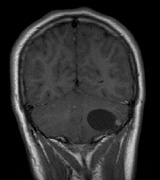

Optic nerve gliomas may involve the optic chiasm and be associated with endocrine disorders or nystagmus.68–70 Surgical excision of chiasmal gliomas (Fig. 6) carries a high risk of visual loss. Invasion of the hypothalamus or the third ventricle carries a poor prognosis, with greater than 50% 15-year mortality rate.71 One review of radiation treatment for chiasmal gliomas collated data from small case series and found no significant long-term improvement in visual function, progression, or mortality with radiation treatment.71 Other reports suggest that radiation doses over 4500cGy improve symptoms and slow progression of chiasmal gliomas over several years.72 Adequate tumor coverage by radiotherapy results in irradiation of normal brain and nearly all children need hormone replacement.73 Chemotherapy is an alternative.74,75

Fig. 6. Surveillance images of a 12-year-old girl with NF1 and an optic nerve glioma which has extended to involve the chiasm. Pre- (a) and postcontrast (b) T1-weighted coronal images reveal a large suprasellar mass with an enhancing component (arrow) seen separately from the normally enhancing pituitary gland. (c) Axial scans through the suprasellar cistern show the tumor is high signal on T2-weighted scans. (d) Enlargement of the chiasm, optic nerve and hypothalamus is visible on the post-contrast T1-weighted sagittal image. Although optic nerve glioma usually has a good prognosis (with visual function often remaining stable in the absence of any intervention66,67), chiasmal involvment is a poor prognostic indicator. A sign of chiasmal involvment may be new onset of endocrine disorders or nystagmus. Surgical excision of chiasmal gliomas carries a high risk of visual loss.68–70